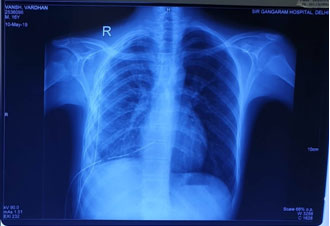

Post operative X-Ray after VATS decortication